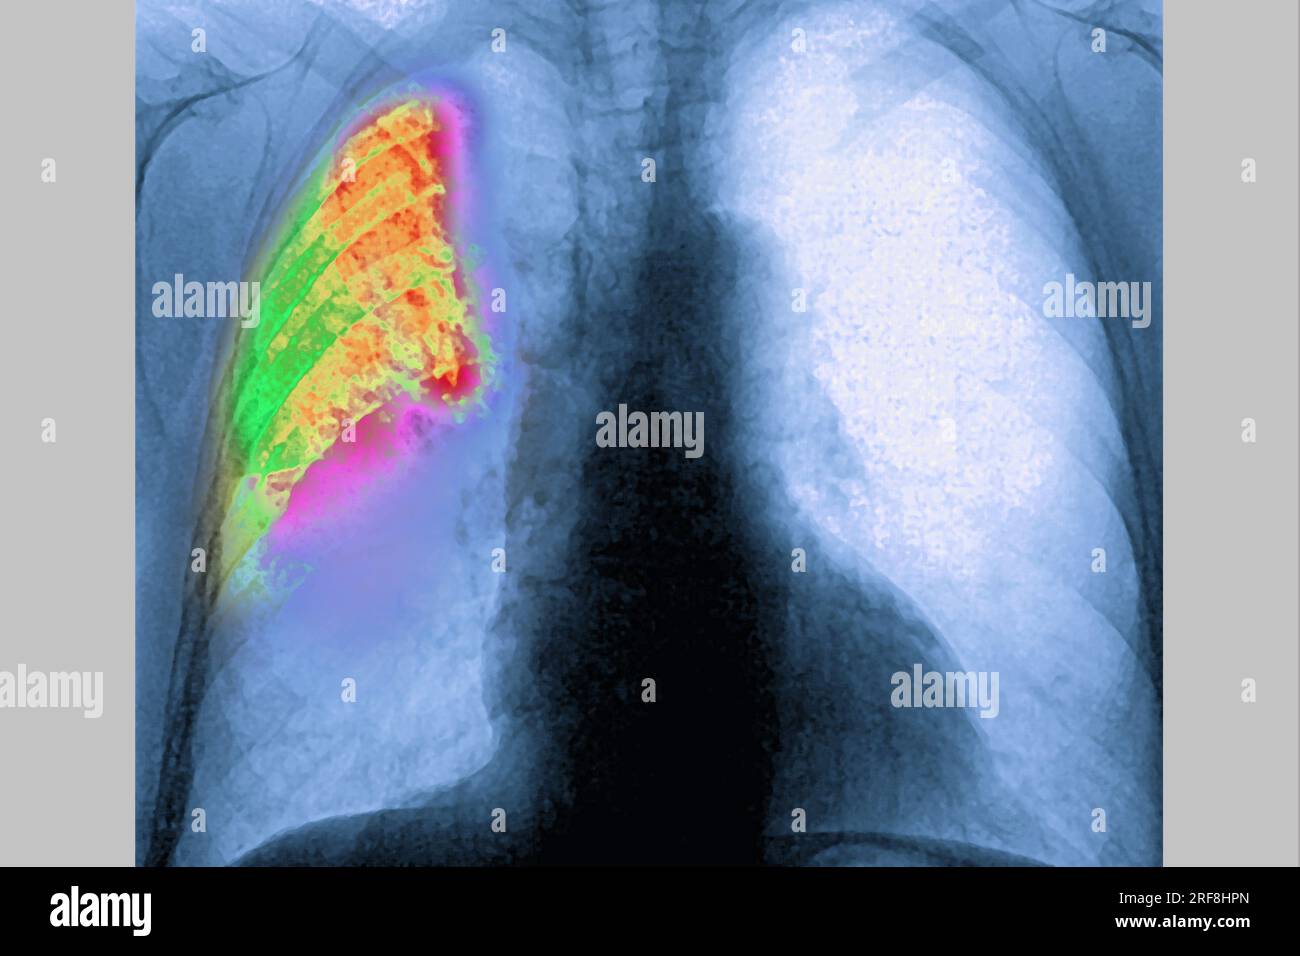

RM2RF8HPN–Pneumonie du poumon droit (infection respiratoire aiguë) révélée par une radiographie thoracique frontale.